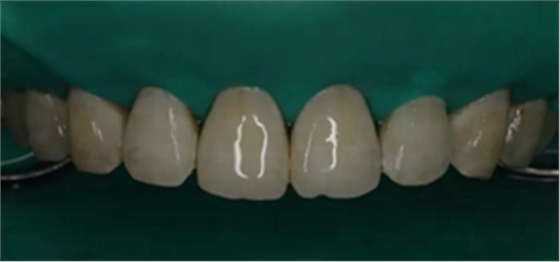

2,使用紅標(biāo)45μm微米和黃標(biāo)25μm粒度車針仔細(xì)緩慢打磨去除釉質(zhì)表面高氟鈣化的斑塊和釉質(zhì)凹坑0.05-0.1mm后,車針打磨后要再使用低速慢機(jī)用矽粒子拋光去除釉質(zhì)表面浮釉(松風(fēng)矽粒子、樹脂拋光輪),下圖是微打磨后。

(下圖是上頜打磨后與下頜術(shù)前未研磨對(duì)比,區(qū)分打磨效果和目的)